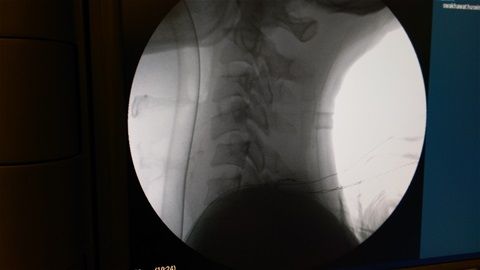

Tραυματικό εξάρθρημα Α6-7 με συνοδό τετραπληγία.

Ο ασθενής προσήλθε μετά από πτώση από ύψος με αδυναμία στα άνω άκρα και πλήρη ακινησία στα κάτω άκρα. Η πρόγνωση βάση της αρχικής νευρολογικής εικόνας θεωρήθηκε πτωχή.